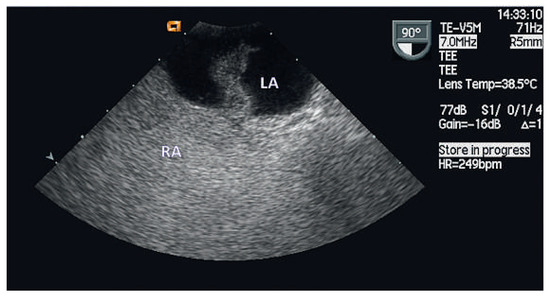

Bachmann Bundle Block Occurring During Radiofrequency Ablation at the Inter-Atrial Septum

A 69-year-old woman was admitted for an elective radiofrequency ablation (RFA) of symptomatic paroxysmal atrial fibrillation, without concomitant structural heart disease except for mild left atrial dilatation [...] Full article